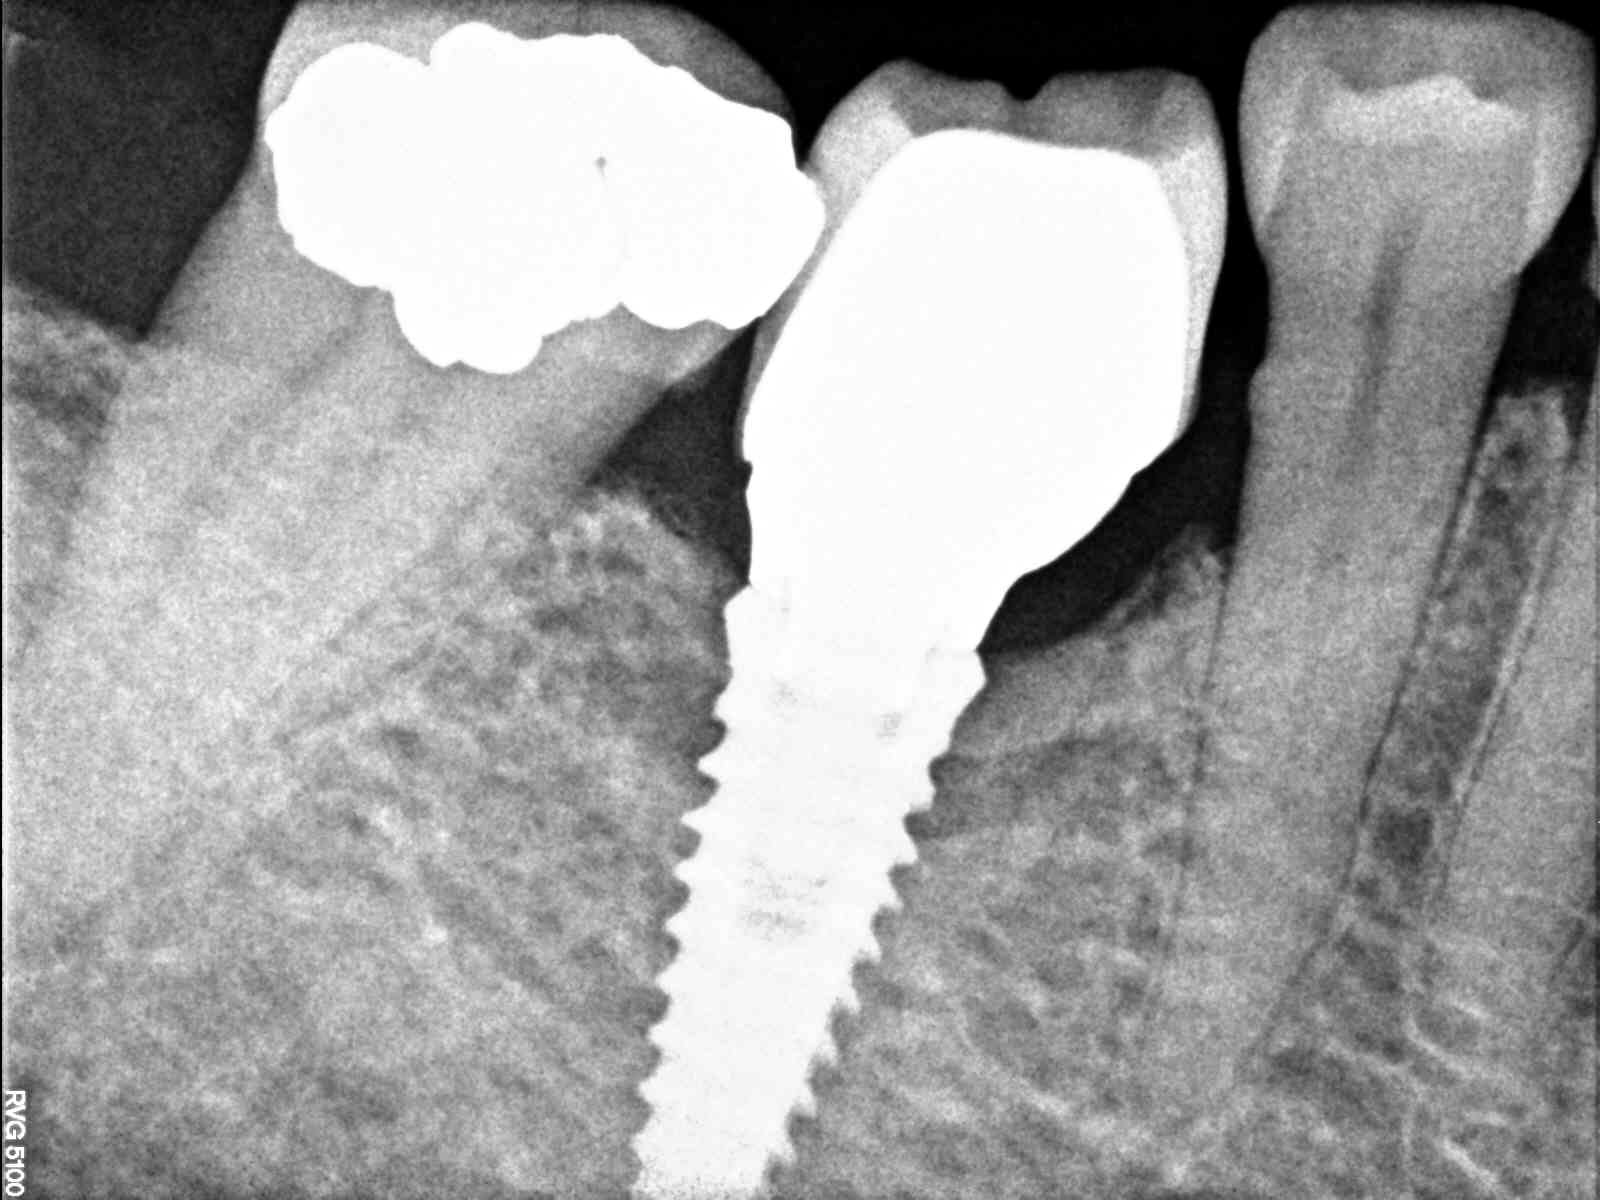

esta paciente se puso los implantes hace aproximandamente 20 años, en la clinica donde se los pusieron le dicen q no tienen su ficha y q pueden ser de 3i, [...]

La paciente cree que el implante es phibo pero no esta segura. por lo que tenemos entendido phibo es compatible con 3I, pero los copings de 3I no nos funcionan. [...]